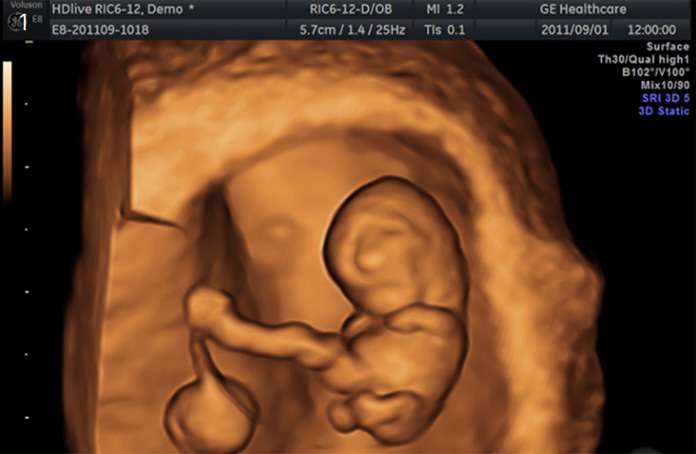

태아 후경부투명대(NT)검사

태아의 기형을 진단하는 기본 초음파검사이며 예약이 필요합니다. 임신 11-13주 사이에 태아의 후경부투명대 두께를 측정하여 태아의 기형아 위험도, ‘다운증후군’ 및 심장기형 등을 알아내는 검사입니다.